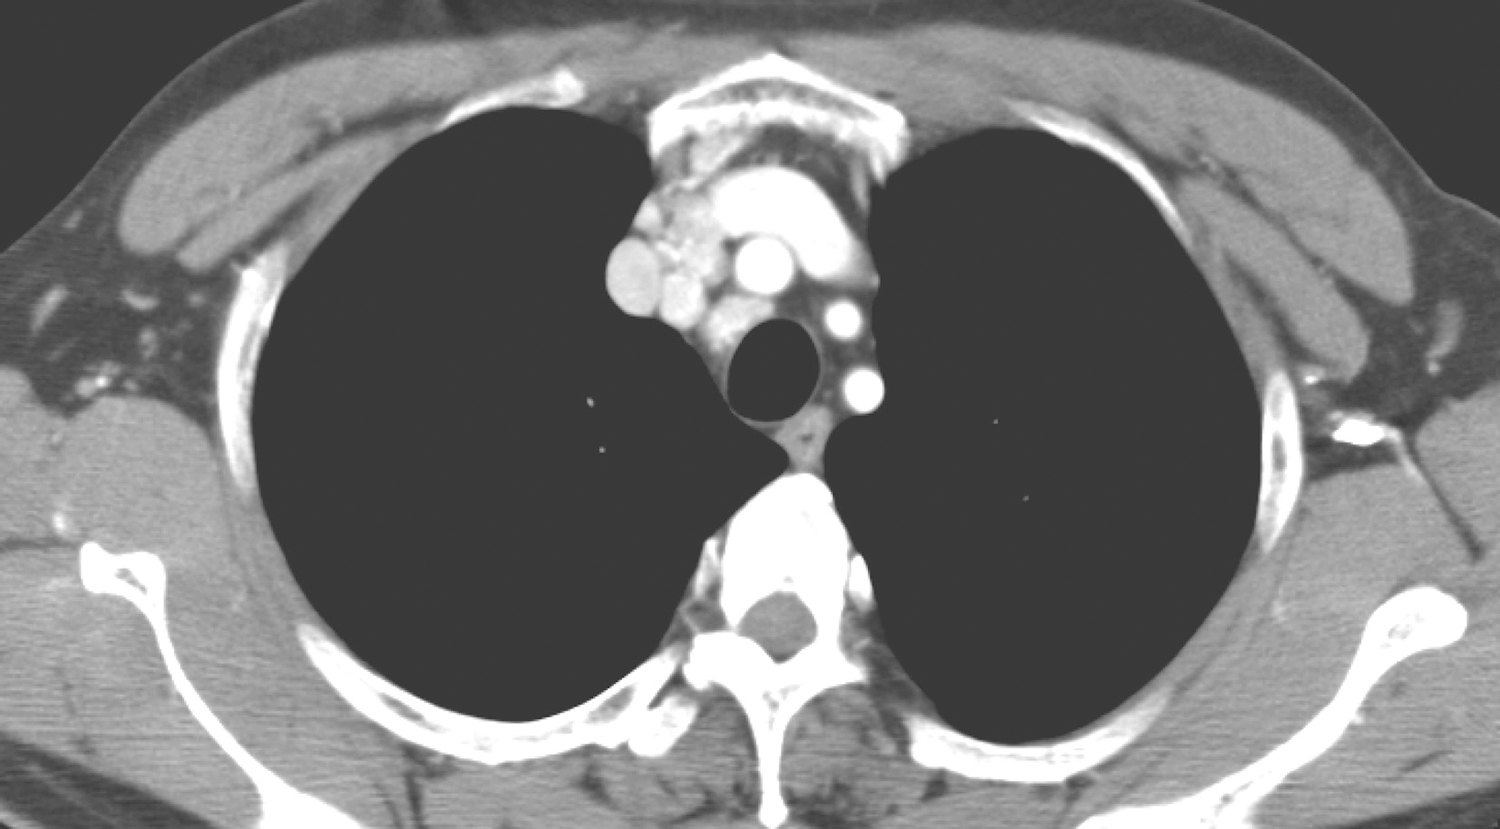

1小时条评论51岁男性,因颈部肿物4个月,伴咳嗽、痰中带血1个月住院治疗。超声检查甲状腺右叶及峡部肿物,如何治疗? 【病例简介】 患者男性,51岁。因颈部肿物4个月,伴咳嗽、痰中带血1个月于2013年6月24日住院治疗。4个月前无意间发现右颈部有一肿物,无肿痛,肿物呈...